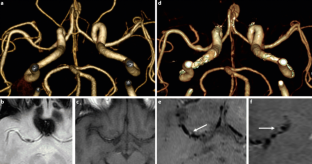

The HR-MRI findings were classified into complete normalization (normal lumen and wall with or without mild enhancement, n = 6), complete normalization with minimal wall changes (focal wall thickening with enhancement but normal luminal angiography, n = 8), incomplete normalization (focal wall thickening with enhancement with dilatation and stenosis on luminal angiography, n = 4), dissecting aneurysm (fusiform aneurysm with residual dissection findings, n = 8) and occlusion (small outer arterial diameter with diffuse contrast enhancement, n = 3).

The use of HR-MRI can demonstrate the distinguishing morphological features of chronic stage of spontaneous and unruptured ICAD as complete normalization, complete normalization with minimal wall changes, incomplete normalization, dissecting aneurysm and occlusion.